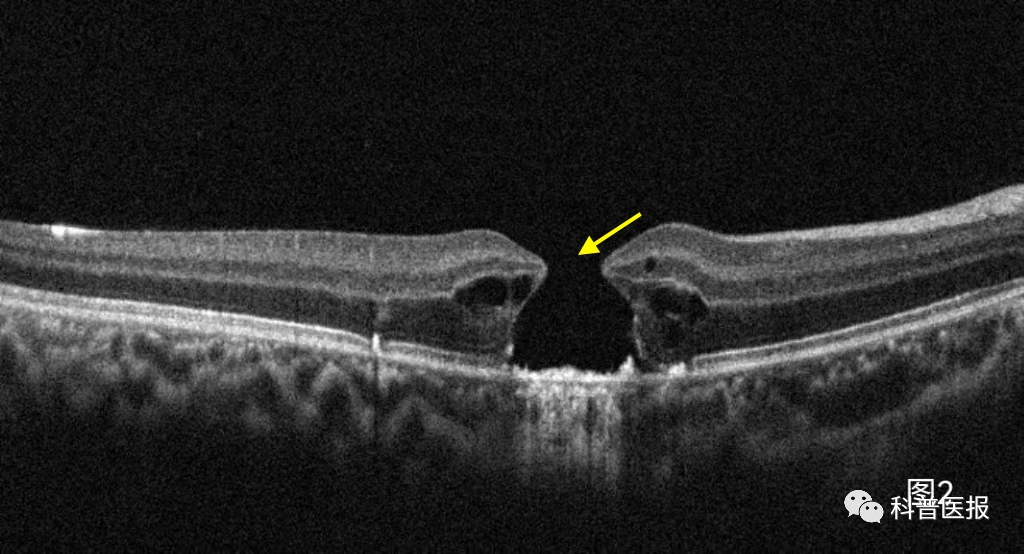

最近,我接诊了一个叫小温的12岁男孩,发现左眼视力下降,配眼镜时矫正视力只有0.7,所以被介绍到我诊室做进一步检查。详细询问小温情况后得知他除了左眼视物模糊,还伴有眼前中央固定白影遮挡,眼底OCT检查,可见黄斑中心外层组织部分缺损(图1)。详细追问病史得知,小温自己在路边摊偷偷买了激光笔,平时在学校和小朋友们相互照射玩耍,视力下降已有半年多,却一直没敢和父母说,最后小温确诊为左眼光损伤。看完这个小病人,不由得让我想起前一个月门诊还看过一个类似病情的小女孩,甚至一年前还有一个男孩因为激光笔损伤造成一眼黄斑裂孔后来做了手术(图2),遗憾的是术后视力也不能恢复。这些接二连三发生的事情,促使我想和小朋友和家长朋友们说点什么。

图2 激光笔照射后导致黄斑全层裂孔(黄箭头)